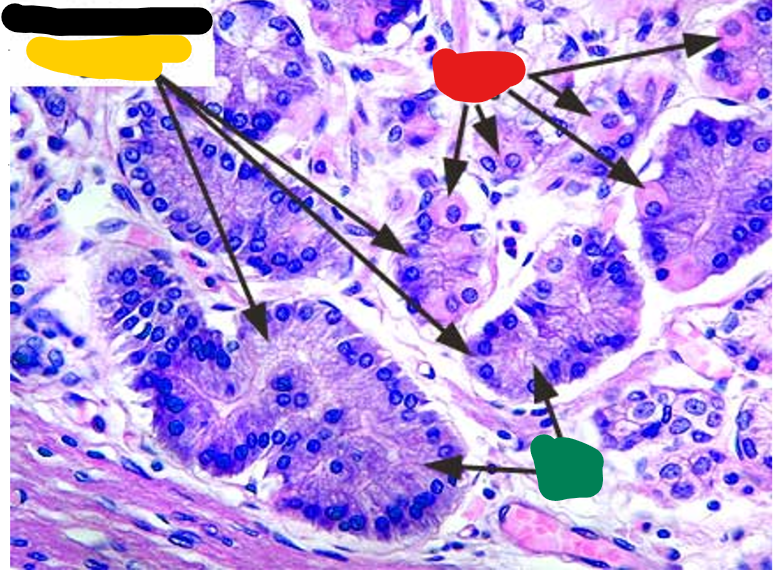

yellow

base of fundic glands

red

parietal cells

green

chief cells

Stomach pyloric region